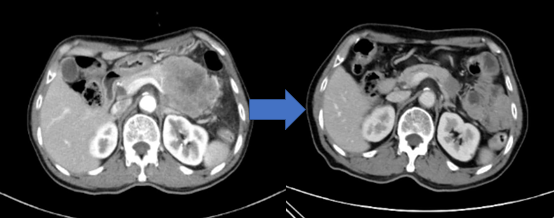

图7

22岁女性患者,2018年瑞金医院就诊,诊断胰腺神经内分泌肿瘤G3伴弥漫肝转移。经瑞金医院胰腺神经内分泌肿瘤多学科团队会诊明确诊断并予以卡培他滨联合替莫唑胺口服化疗,服药12个月肿瘤达到完全缓解,原发病灶及转移病灶消失,目前肿瘤持续缓解。左图为口服化疗前影像(弥漫肝转移),右图为药物治疗12个月的影像(转移病灶完全缓解)。